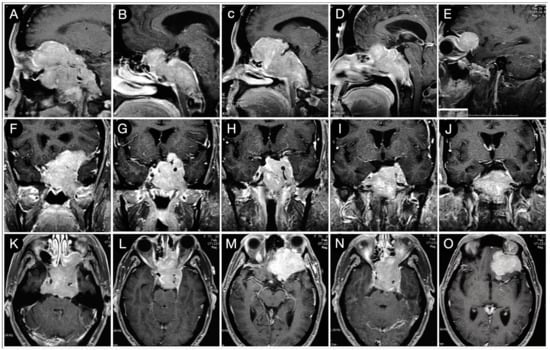

Case #1: Infradiaphragmantic Tumor with Middle Fossa Involvement through the Cavernous Sinus

3.2.1. Case #2: Involvement of the Anterior Skull Base

3.2.2. Case #3: Paramedian Pattern of Growth with Parenchymal Invasion

3.3.1. Case #4: Involvement of the Middle Skull Base with Parenchymal Invasion

3.3.2. Case #5: Extension beyond the Lateral Wall of the Cavernous Sinus

3.3.3. Case #6: Encasement of the Posterior Communicating and Anterior Choroidal Artery

Case #7: Encasement of the Paraclinoid and Supraclinoid Internal Carotid Artery

Case #8: Aggressive ACTH Tumor with Multiple Recurrences